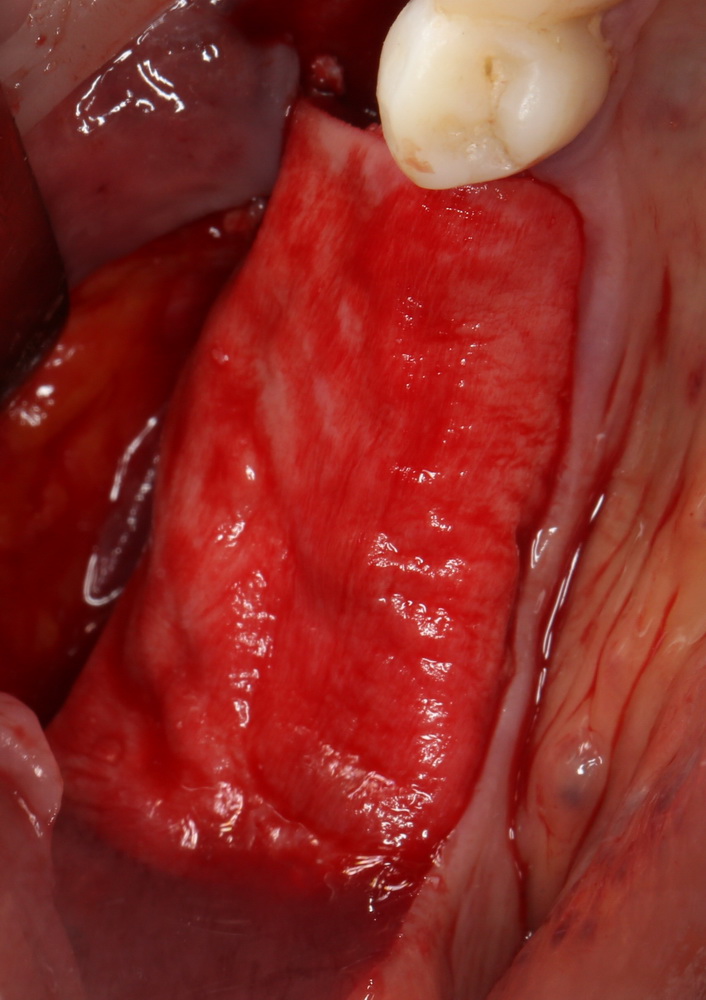

Исходная ситуация:

Другими словами, альвеолярного гребня нет вообще).

Скелетируем кость нижней челюсти: